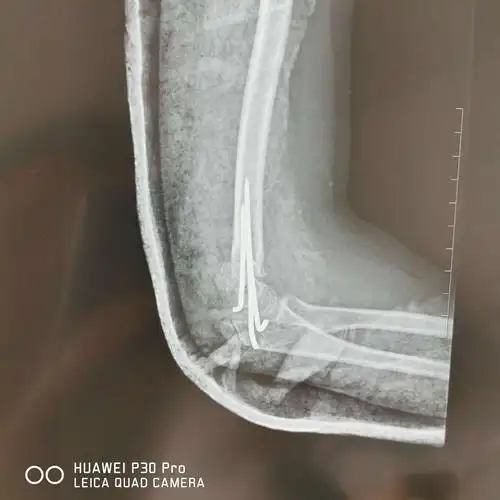

儿童肱骨髁上骨折(屈曲型)

儿童肱骨髁上骨折gartland4型

iv:屈曲性肱骨髁上骨折,侧位片肱骨前缘线后移于肱骨小头不同类型的

左侧肱骨髁上骨折一例

肱骨髁上骨折

桡a搏动弱,手指触觉减退,伸拇肌力m4;诊断"肱骨髁上骨折 伸直桡偏型

肱骨髁上骨折一例